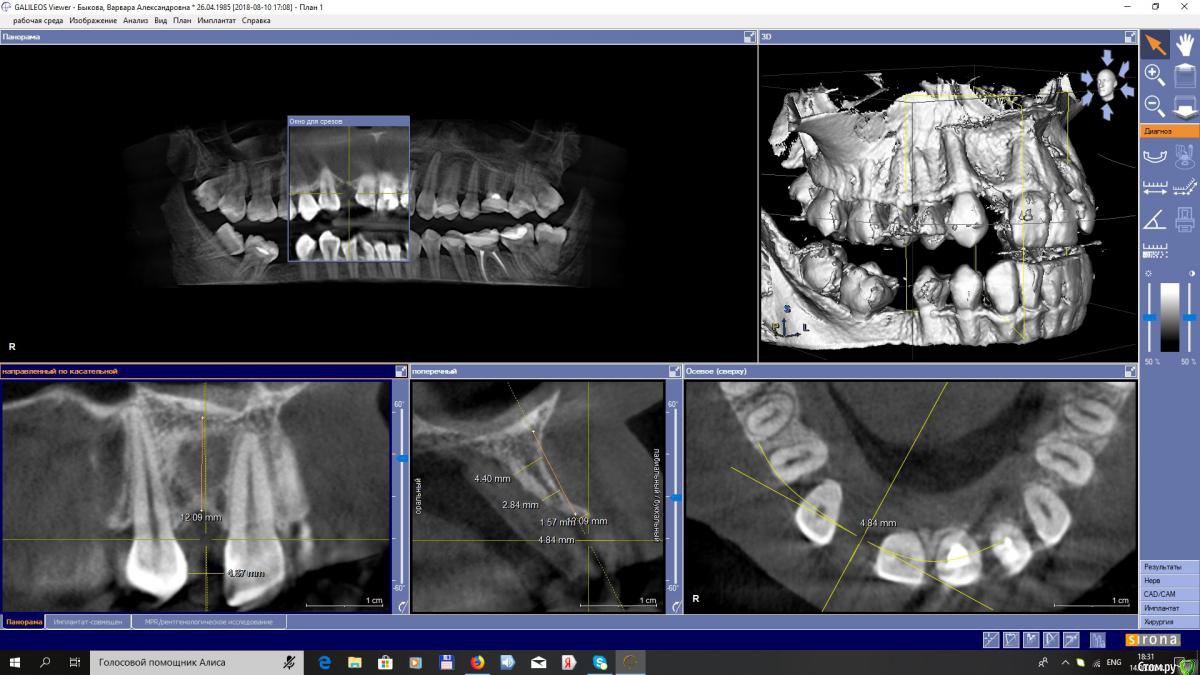

EEcho Опубликовано 27 августа, 2018 Поделиться Опубликовано 27 августа, 2018 Варианты решения данной ситуации?Пациентка хочет импланты, но не хочет обращатся к ортодонту.Что посоветуете? Ссылка на комментарий

Иван911 Опубликовано 29 августа, 2018 Поделиться Опубликовано 29 августа, 2018 Варианты решения данной ситуации?Пациентка хочет импланты, но не хочет обращатся к ортодонту.Что посоветуете?Уточните чего хочет пациент , если она не хочет ничего менять- это тоже ее право, средняя ширина латеральных резцов 5-6мм , у вас почти 5 мм расстояние - можно на крайний случай подполировать соседние зубы. показать пациенту все на wax-up , если все устраивает подписывает план лечения то Straumann 2.9 + Кость + десна,если надо на 2 этапе корекция десны. 2 Ссылка на комментарий

EEcho Опубликовано 29 августа, 2018 Автор Поделиться Опубликовано 29 августа, 2018 22 у нее развернут, на 12 носит бабочку, развернутые двойки ее устраивают. к ортодонту категорически не хочет и не хочет точить свои зубы.На 22 еще и киста, планирую удалять 22. Ссылка на комментарий